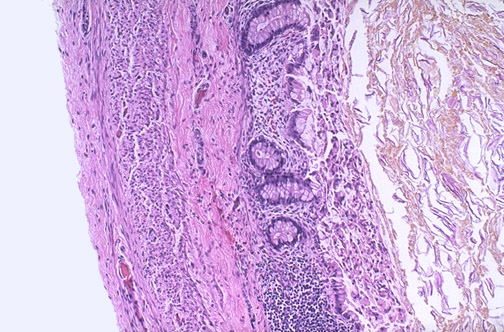

| This is normal fetal colon at low magnification with mucosa containing crypts with abundant goblet cells. There is an underlying submucosa with abundant lymphoid tissue and beneath this a muscularis. Note that the lumen is filled with faint brown-orange meconium. |